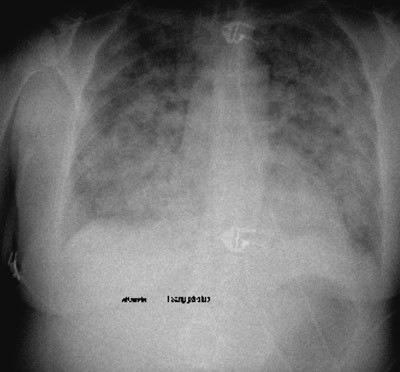

Røntgen thorax viste utbredte konfluerende fortetninger (fig 1). CT abdomen og CT thorax viste noe væske omkring høyre nyre, litt perikard- og pleuravæske og lett dilatert høyre colonhalvdel og transversum, ingen holdepunkter for lungeemboli. Ekkokardiografi viste velfungerende myokard og klaffeapparat uten mistanke om endokarditt. Hun ble overflyttet til intensivavdelingen. Etter noen timer måtte hun intuberes og tilkobles respirator på grunn av respirasjonssvikt.